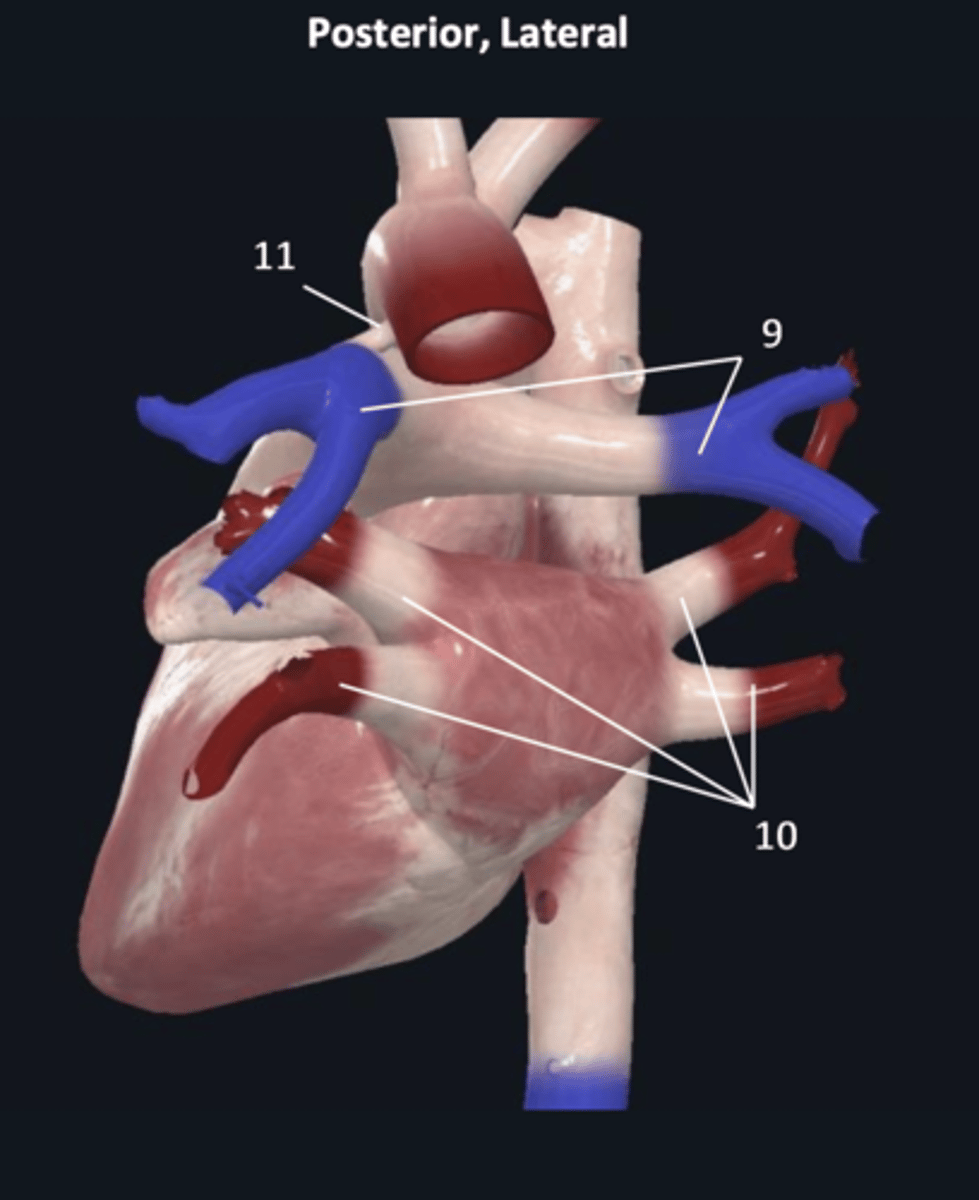

pulmonary trunk

8

pulmonary arteries

9

pulmonary veins

10

ligamentum arteriosum

11

right coronary artery

1 (red)

great cardiac vein

3

posterior left ventricular artery

6

posterior vein of left ventricle

7

coronary sinus

8

right posterolateral artery

9

middle cardiac vein

10

posterior interventricular artery

11

right marginal artery

12

small cardiac vein

13